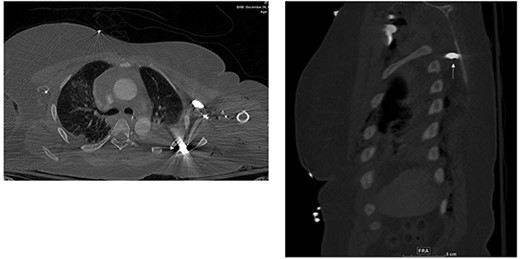

Abdomen and pelvis CT showed an intra-abdominal bullet fragment abutting the anterior gastric wall without gastric injury and a minor splenic laceration. Also, a bullet fragment in the right distal external iliac artery at the level of bifurcation (Fig. 5) causing a filling defect, however no extravasation, and the contrast passed to the superficial femoral arteries (Fig. 6).

Filling defect in the external iliac artery with no extravasation and the contrast passing to the superficial femoral arteries.